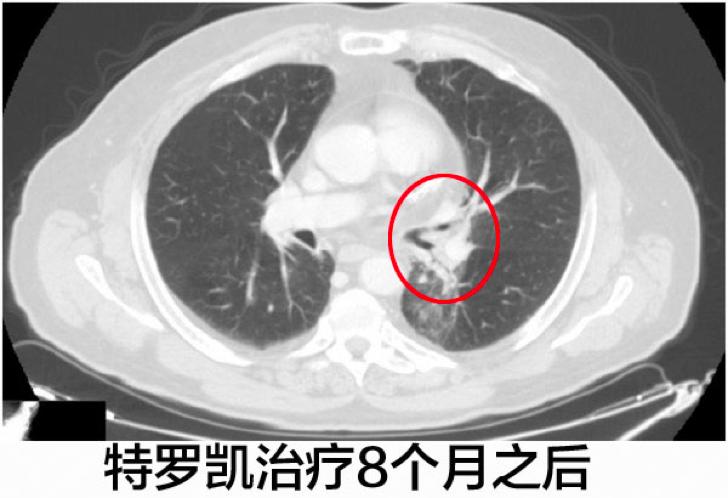

患者继续使用特罗凯进行治疗,四个月之后的CT影像学检查发现左肺下叶肿瘤显著缩小,至7毫米。

在最后一次CT影像学扫描,左肺下叶导致呼吸困难的区域还能辨识的出来,但是实体肿瘤几乎不见了,特罗凯治疗1年之后达到了完全的缓解。